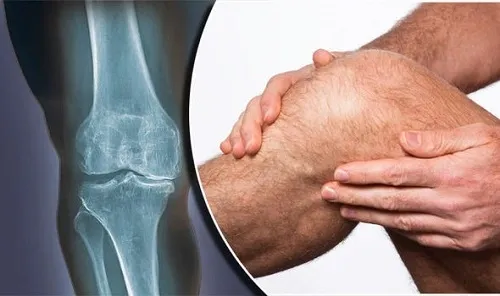

بنابراین میتوان اینطور برداشت کرد که زانو درد و بیماریهای به وجود آورنده آن، میتواند در هر سنی فرد را درگیر کند؛ حتی در ۴۰ سالگی. این مشکل، میتواند منشاهای متفاوتی داشته باشد.

میتواند در اثر ساییدگی به وجود بیاید و یا حتی دلیل اصلی آن پارگی مینیسک باشد. در این مطلب به بررسی علائم و علل زانو درد در سنین پایین میپردازیم و در پایان توصیههایی را برای پیشگیری از مواجه شدن با این درد به شما ارائه خواهیم کرد.

بررسی شایعترین دلایل زانو درد در چهل سالگی

زانو درد زودرس اغلب به دلیل ساییدگی و پارگی مفاصل در طول زمان، ایجاد میشود؛ اما دلایل بسیار دیگری نیز وجود دارند که میتوانند منجر به ایجاد چنین عارضهای شوند. برخی از این موارد عبارتاند از: